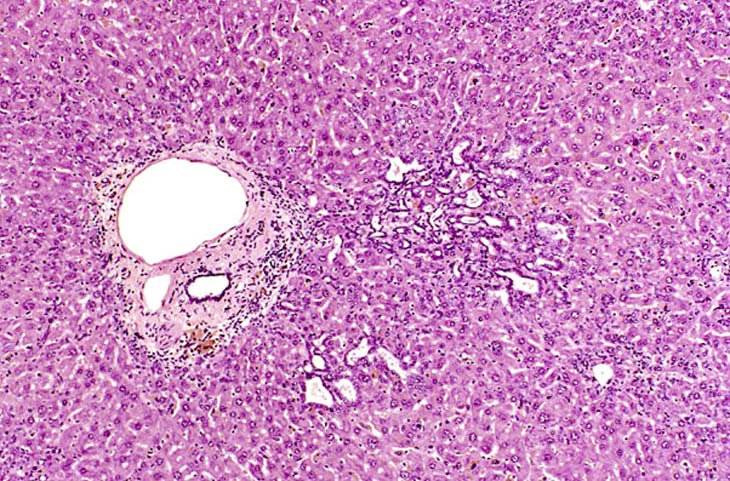

While most examples of bile duct hyperplasia consist of a modest duplication of normal appearing bile ducts in portal areas, occasionally more dramatic examples are found in other areas of the hepatic lobule.

Two local aggregates of proliferating bile ducts within the hepatic lobule.